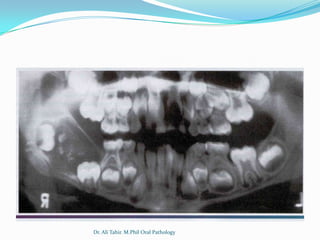

Radiographic

 Compound

 Unilocular, containing multiple radiopaque structures

resembling miniature teeth

 May contain 2-3 or upto 20-30 tooth like structures

 Complex:

 Unilocular,usually small but may grow upto 10cm

 Solid radiopaque mass

 Surrounded by thin zone of radiolucency

 Cortication

 Usually associated with

an unerupted tooth

 A developing odontoma

may be radiolucent

 Radiographic findings

are usually diagnostic